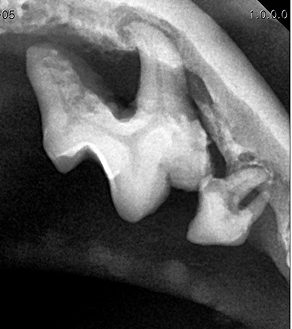

치주염 치료는 진행 단계에 따라 다르게 접근합니다.

BEFORE

AFTER